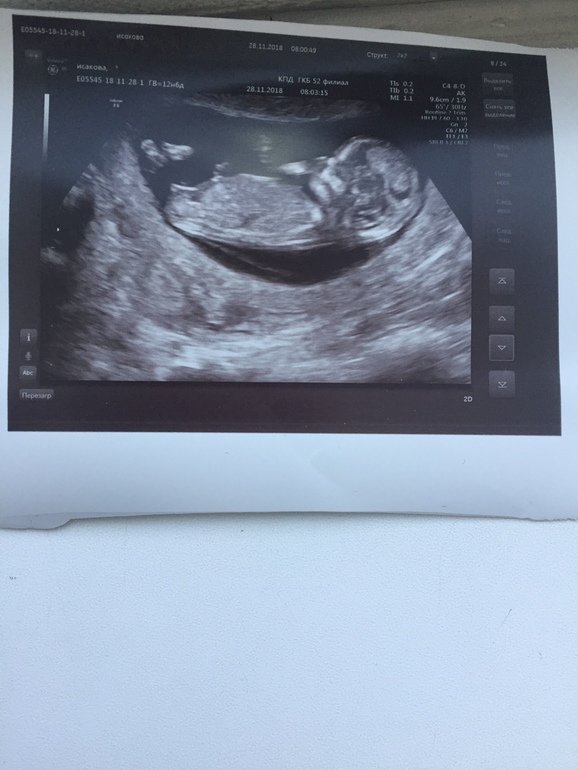

Пол малышаУЗИ в 12.6, реально ли понять пол ребёнка и насколько будет правда

Узистка когда смотрела, сказала что не видно ещё

Понимаю, что не в таком ракурсе нужно смотреть

По твоему снимку я не вижу ничего 🙈🤷